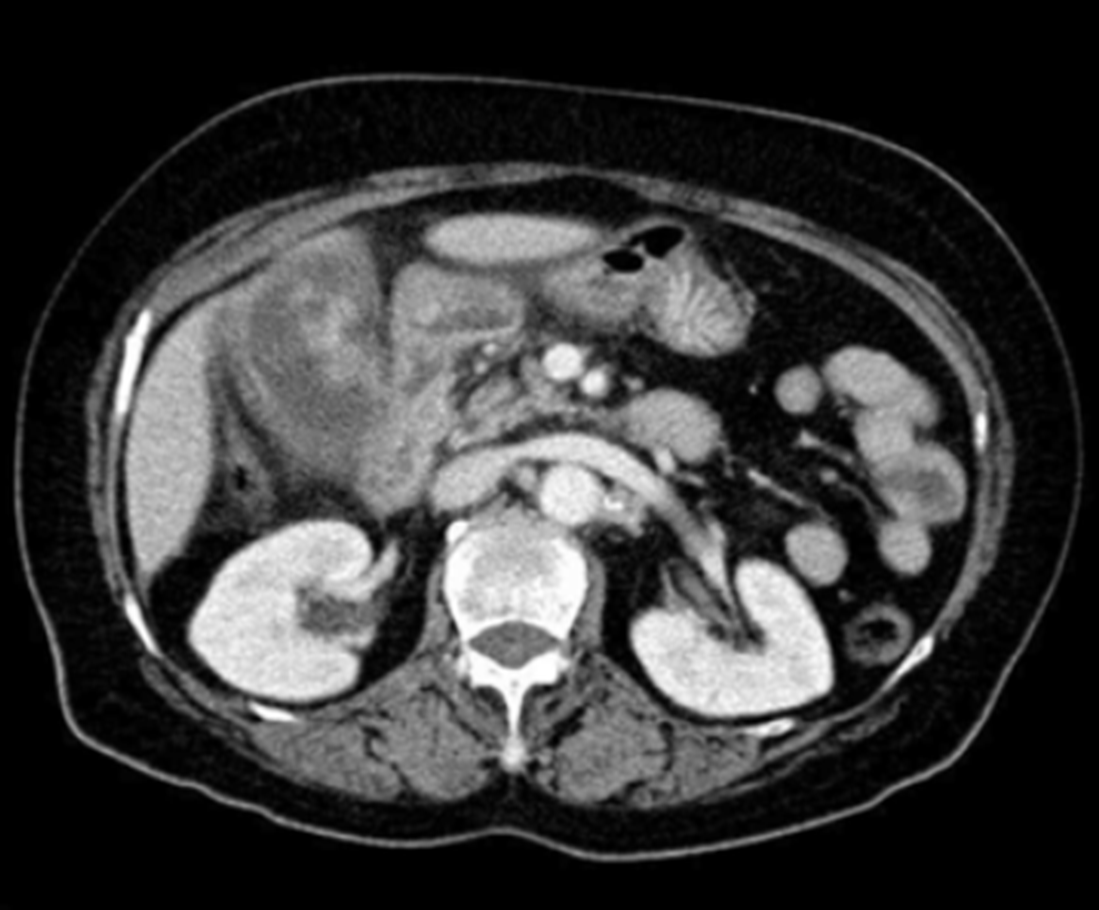

CT: 2-3 cm irregular margin mass in the gallbladder

• 병기 설정을 위해 시행한 CT에서 portal vein 침범이나 간의 광범위한 침윤 소견이 확인되지 않았으므로 절제가능한 병변으로 판단된다.